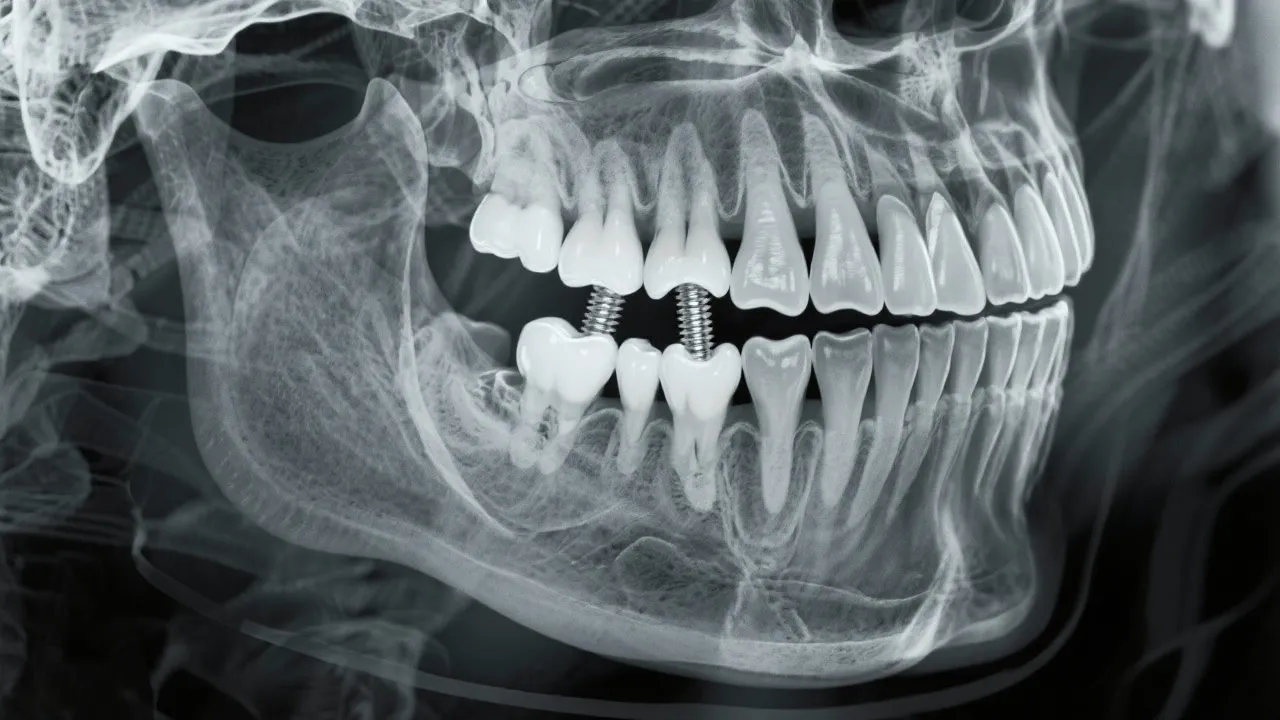

This thorough guide explores the crucial relationship between bone density and dental implants. Bone density plays an integral role in implant success, determining the stability and integration of the implant into the jawbone. Understanding this connection aids in making informed decisions regarding dental health.

Bone density is a critical factor when considering dental implants. It refers to the amount of bone material present in a specific volume of bone, which directly impacts an implant's stability and longevity. Adequate bone density ensures that the dental implant can support the forces of chewing and other oral functions. Inadequate bone density, however, may lead to complications, affecting the implant's success rate. High bone density provides a stronger anchorage point, which is essential for the integration of the implant within the jawbone. When evaluating candidates for dental implants, dentists often conduct imaging studies like X-rays or CT scans to assessbone density patterns and bone structure.

The process of osseointegration, where the implant fuses with the bone, is heavily dependent on bone quality. Denser bone provides better support and integration for the implant. When bone density is insufficient, additional procedures such as bone grafting may be necessary to enhance bone volume and strength, allowing for a successful implantation process. Each step of the osseointegration process is crucial and requires careful monitoring. We must remember that bone health is not entirely static; it can fluctuate based on lifestyle choices, hormonal changes, or medical conditions. Therefore, maintaining a strong and healthy jawbone is vital not only before receiving implants but also as an ongoing health measure.

Impact of Bone Density on Implant Success

Successful dental implantation requires not only the technical skill of the dental surgeon but also the biological readiness of the patient’s jawbone. High bone density provides a solid foundation for implants, reducing the likelihood of structural failure. Despite the importance of bone density, many patients may be deterred by recommendations for additional procedures like grafting. Understanding how these interventions can lead to better long-term results is essential for informed decision-making.

In cases where bone density is questionable, preemptive measures such as bone grafting or the use of mini implants may be considered. Mini implants, which are narrower in design, can sometimes be placed without extensive grafting procedures; however, they may not be suitable for all patients or types of restorations. Collaborating closely with your dental team can help to devise the best approach tailored to your specific situation.